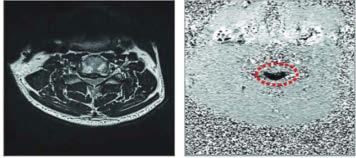

52 Neue Diagnoseverfahren bei Rückenmarkskompression: Liquordruck-Analyse und Phasenkontrast-MRI